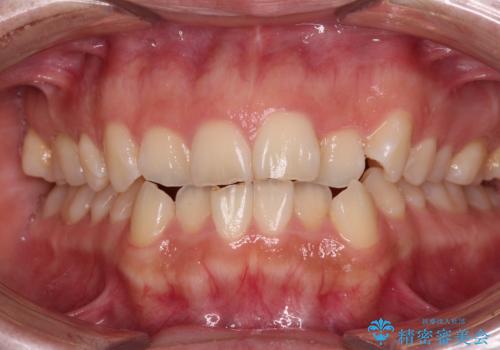

[ 矯正治療 ] 噛み合わせ前歯の見た目をきれいにしたい

![[ 矯正治療 ] 噛み合わせ前歯の見た目をきれいにしたいの症例 治療前](https://seimitsushinbi.jp/wp/wp-content/uploads/2025/08/IMG_7266-500x350.jpg?v=1754654745)